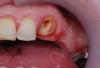

Doc Опубликовано 28 октября, 2008 Поделиться Опубликовано 28 октября, 2008 Клинический случай: Пациент М., явился в 1999 году для санации и протезирования. В те времена имплантацией я еще не увлекался, потому пришлось делать мостовидный протез 23--26,27. 23 зуб был интактным, депульпирован потому, что после обработки стал очень сильно реагировать на температурные раздражители, в общем не выдержал обработки. Доктор (один из лучших моих коллег) депульпировал и установил СВШ, т.к. жалко было интактный зуб пускать под вкладку. Протезирование было закончено то ли в конце 1999 года, то ли в самом начале 2000, сейчас точно не помню. Две недели назад пациент явился с жалобами на подвижность в области 23 зуба. При помощи Коронафлекса мост был сбит с 26 и 27 зубов. Открывшаяся картина была такой: При этом от интактного зуба не осталось практически ничего. С огромным трудом удалось обработать под ВКВ, не уйдя совсем под десну по всей окружности. Все было мягкое и протыкалось простым зондом. После обработки выглядело вот так: При этом, чтобы меня не обвинили в том, что я не умею фиксировать мосты, что у меня цемент левый и все такое, могу показать как себя вели эти восемь-девять лет зубы с вкладками под тем же самым мостом, с тем же самым цементом, установленные в тот же самый день. Согласитесь, что разница однозначно не в пользу СВШ. Вкладки, как видите, вместе с зубом чувствуют себя идеально. И это после довольно сильной работы Коронафлекса! При подобной параллельности стенок мост сбить было очень и очень непросто! Практически без новой обработки можно сажать новые коронки и будет ему счастье на всю оставшуюся жизнь. Если бы не тройка (вернее, если бы на тройку тоже была изготовлена вкладка девять лет назад), то этот мост стоял бы еще долго и счастливо. А теперь пришлось ставить два имплантата, делать вкладку на тройку и молиться, чтобы размягченный дентин под новой вкладкой и коронкой не продолжал гнить. Так что, коллеги, как не кажется смешным мнение Корабахтова о том, что "рядом с СВШ все гниет", а он прав. Это просто один из многих-многих случаев. Просто он был буквально пару недель назад и совсем свежий. Таких штифтов я уже повынимал немеряно! А вот чтобы вокруг вкладки так сильно сгнил корень, такого я не помню (если, конечно, вкладка была сделана по всем правилам). P.S. Эти вкладки были установлены на Гарвард, кстати! Современные цементы куда круче, а следовательно, если на древнем фосфат-цементе видим такую картину, то на современных стеклоиономерах и разных гибридных композитах это должно вообще стоять вечно! 1 Ссылка на комментарий